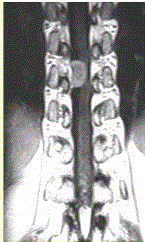

问题 患者女,52岁,颈部不适2年。MRI检查结果如下图。 观察所给出的MRI影像,对病变定位、定性诊断有意义的征象包括

选项 A.病变水平脊髓受压变细 B.病变与脊髓关系不清晰 C.病变上下方蛛网膜下腔增宽 D.矢状位示病变周围蛛网膜下腔无变化 E.脊髓向健侧移位 F.病变明显均匀强化 G.未见病变向椎间孔延伸

答案 ACEFG

解析 ACEFG